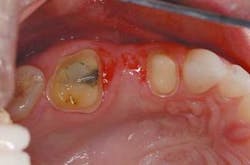

Tooth No. 14 had been previously restored with a five-surface amalgam. The buccal cusps were undermined with supragingival cracks. Further, there was recurrent caries, starting at the gingival margin on the distal. Tooth No. 12 was a virgin premolar, and it was decided to sacrifice the integrity of this tooth for what appeared to be a predictable abutment for a three-unit bridge.

On the preparation day, the patient was anesthetized with one carpule of 2 percent Septocaine. Both bridge abutments were prepared the same way with 1.5 mm occlusal reduction prepared with a KS 2 coarse 1.4 mm round-tipped, straight diamond bur (Brasseler) and a coarse diamond football (Brasseler). The facial and lingual surfaces were prepared with a KS 2 coarse, followed by a KS 1 fine for smoothing and final contouring. The inter-proximal contacts were prepared with a KS 0 coarse 1.0 mm round-tipped, straight diamond bur (Brasseler). Although crack propagation may not be a concern with the Lava All-Ceramic System, which was utilized to develop the bridge, still prepare the teeth to be very smooth with no sharp angles to potentially propagate any cracks. The depth of reduction in the photos may seem minimal based on the shape of the original teeth. However, because the plan in the wax-up was to fill out the buccal corridor, the depth cuts were based on a thickness determined by the final wax contour, not the original tooth contour.

In this case, no retraction cord was necessary because of the supragingival margins. An impression was taken with 3M ESPE's Impregum™ and Permadyne™ impression materials.